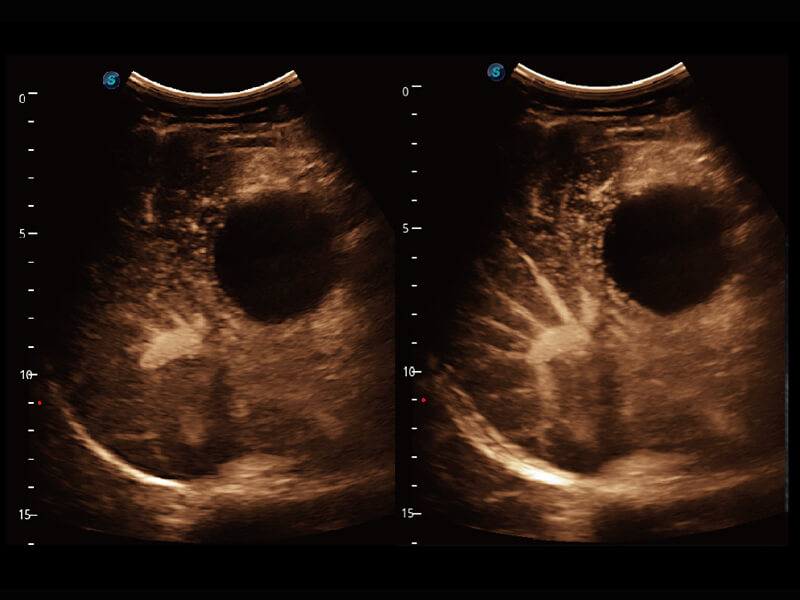

S60探头工艺,从前端信号处理每一个环节采集无损声学数据,真实还原组织原貌,再现解剖细节。

• 新型复合材料探头( 12L-A )

临床图